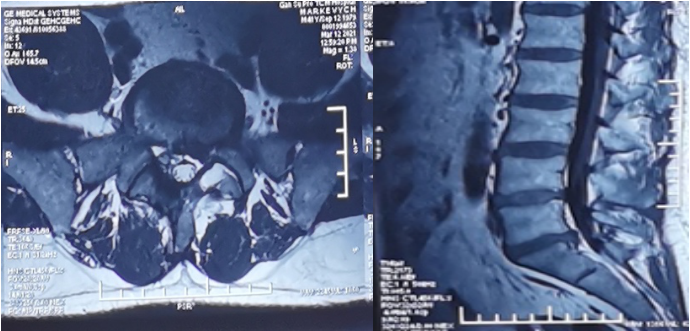

患者男性,41岁,系兰州交通大学乌克兰籍在读博士,因“腰痛伴左下肢疼痛、麻木1月余,加重1周”收住。该患者1月前出现腰痛伴左下肢疼痛、麻木症状,经针灸、理疗、口服药物等保守治疗后,疼痛未见缓解。1周前,症状加重,不能行走。病痛给他的日常生活和工作造成了极大的困扰,几经辗转,来到我院门诊就诊。进行了细致地查体后,明确诊断:1.腰椎间盘突出伴有神经根病(L5/S1,左侧);2.腰椎间盘突出症术后(L4/5);3.椎体终板炎(L5/S1)。结合病史临床表现及影像学检查,经与患者及家属充分沟通后收住入院。经完善相关检查后,于4月8日下午行全麻经皮脊柱内镜下经椎板间入路髓核摘除神经根减压术(L5/S1,左侧),术后患者腰痛及左下肢疼痛消失,平卧6小时后,患者配戴腰围下地活动,无特殊不适,患者对手术疗效非常满意。

术前X线片

术前CT

术前MRI